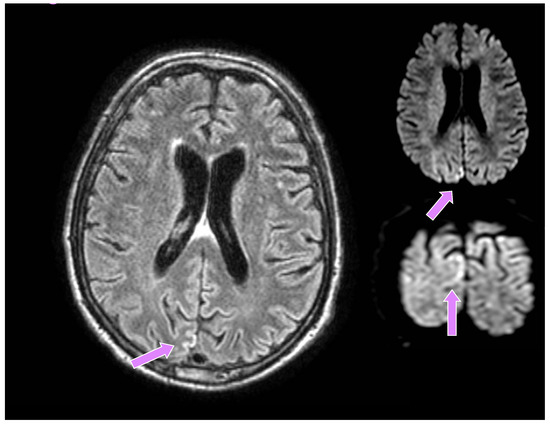

A 66-year-old man from a closed community in northern Italy was admitted to our university hospital for visual disturbances and left-sided migraine headache without additional focal or lateral neurological deficits. These symptoms had started a few weeks before in association with high blood pressure. His medical history showed poorly controlled arterial hypertension, reduced coronary reserve and REM sleep behavioural disorders (RBD), which started about six months earlier and were treated with carbamazepine, subsequently suspended by the patient. He had a negative family history for neurodegenerative diseases. A brain CT did not show any recent lesions, while supra-aortic trunk echocolordoppler showed a 45% right internal carotid artery (ICA) stenosis, and a brain MRI documented signs of chronic microangiopathy. Owing to episodes of blurred vision, a campimetry examination was performed which showed a right lateral hemianopsia. He was then transferred to the neurology unit, where he underwent a brain contrast-enhanced MRI, the DWI sequences of which revealed a tenuous hyperlucency in the occipital cortical site, mainly parasagittal on the right (much less evident and shaded in the contralateral site), corresponding to a tenuous hyperintensity in FLAIR, slightly less recognizable if compared to the previous examination (Figure 1).

Figure 1. Brain MRI: altered signal in the occipital region, mainly parasagittal on the right, much less evident and shaded in the contralateral site (Seq. FLAIR, Axial and Coronal DWI), highlighted by pink arrows.

There are two aspects to consider: firstly, the presence of RBD can sometimes be a marker of neurodegeneration, predictive for the development of synucleinopathies or, indeed, CJD [18]; the clinical evolution, neuroimaging data and EEG abnormalities seemed more consistent with the second hypothesis, so the diagnostic pathway for prion diseases was followed. Secondly, the first EEG (i.e., recurrent paroxysmal abnormalities in the posterior regions with diffusion to the homologous contralateral regions with a periodic trend), although not totally specific, could point towards the correct diagnostic hypothesis when the symptoms were characterised almost only by visual disturbances. Furthermore, the neuroradiological data, especially in this particular clinical context (i.e., poorly controlled arterial hypertension and onset of symptoms in the context of hypertensive crisis) and considering the large variability in neuroimaging of PRES, initially seemed consistent with this diagnosis, documenting a tenuous hyperlucency in the occipital cortical site in DWI sequences, corresponding to a tenuous hyperintensity in FLAIR. Indeed, although a brain MRI generally provides useful hints to distinguish PRES from the Heidenhain Variant, since the posterior subcortical involvement evidenced by the typical hyperintensity usually occurs during the course of PRES, and not in CJD, PRES can manifest itself with many less typical neuroradiological findings (e.g., restricted diffusion, lesions at different cortical sites, basal ganglia, etc.) [19]. Therefore, neuroimaging is generally not sufficient in the differential diagnosis of PRES, and also anamnestic and clinical data must be considered, which, in this particular case, proved to be misleading.